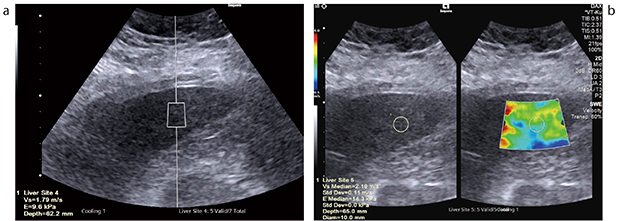

図2 高度肥満患者(NASH,皮下厚4.5cm)におけるDAXを用いた肝硬度計測

a:ポイント・シアウェーブエラストグラフィ b:2Dシアウェーブエラストグラフィ

(画像ご提供:岩手医科大学消化器内科・黒田英克先生)